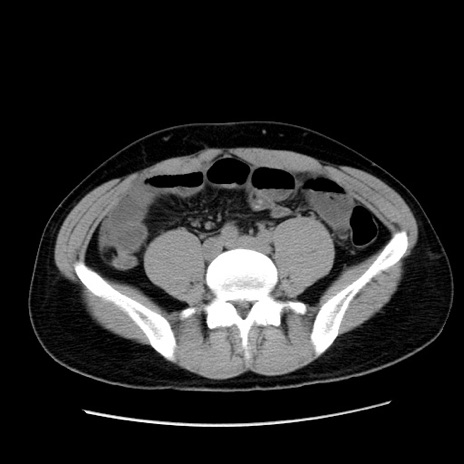

症例36(横断像)

【症例】20歳代 男性

【主訴】心窩部痛

【現病歴】今朝より上腹部痛あり。一旦軽快していたが再度出現したため救急要請。昨日夕に白身の魚を含む刺身を食べた。

【身体所見】BP 136/89mmHg、HR 74/min、BT 37.0℃、腹部:膨満、軟、心窩部に圧痛あり。反跳痛なし、筋性防御なし、腸雑音やや亢進あり。

【データ】WBC 17700、CRP 0.48